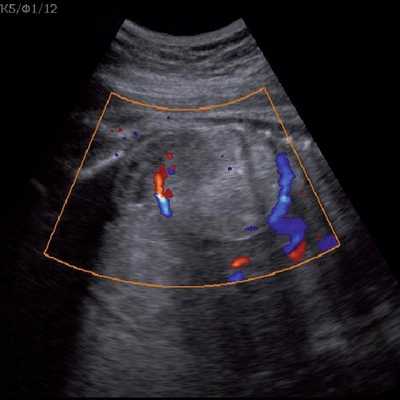

Под диафрагмой справа визуализировалось гиперэхогенное опухолевидное образование несколько неоднородной солидной структуры, с четкими ровными контурами, размером 50x38x35 мм. К нижнему полюсу данного образования прилежала правая почка, имеющая нормальные размеры, форму и структуру. Нижняя полая вена была смещена кпереди и влево. Обращала на себя внимание выраженная гепатомегалия, причем структура печени не была однородной. Она содержала множественные гиперэхогенные включения размерами до 17 мм, окруженные тонким гипоэхогенным периферическим ободком. Цветовое допплеровское картирование(ЦДК) демонстрировало интенсивную периферическую васкуляризацию опухоли (рис. 1-3).

Рис. 2. Кровоток в нейробластоме плода. Цветовое допплеровское картирование. Отчетливо виден питающий сосуд, огибающий образование по его периферии. К нижнему полюсу образования прилежит интактная почка плода.